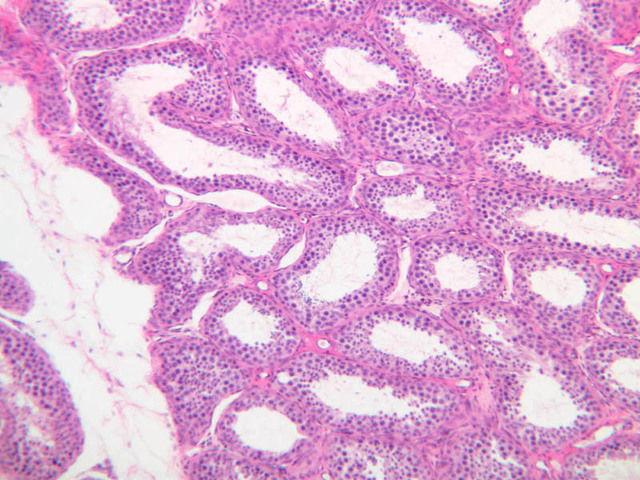

Scan a section of testis from the slide boxes at low magnification, and note the arrangement of the testicular components (slide B-80, H&E [1x-labeled, 1x, 1x]; B-81, PAS [1x, 1x]; B-82, adult monkey testis, H&E [1x, 1x, 1x, 1x, 1x] [2.5x, 10x]). A thick fibroelastic connective tissue capsule, or tunica albuginea, surrounds the testis. Within the tunica and sometimes bulging inward are a number of large blood vessels. The larger, thicker walled vascular profiles are sections through the testicular artery, which executes a highly convoluted course through the tunical plane. Closely applied to the outer surface of the tunica albuginea is the visceral layer of the tunica vaginalis, whose free surface is lined with mesothelium (B-81, PAS [2.5x-labeled]). In some specimens the parietal layer of the tunica vaginalis has been removed, but in others it is possible to find both layers of the tunica vaginalis and the potential serous space between them. How does the tunica vaginalis originate? Connective tissue septa extend inward from the tunica albuginea, subdividing the testis into a number of lobules. Within each lobule are numerous profiles of seminiferous tubules (B-82 [2.5x-labeled, 10x] [20x, 40x]). The interstitial space between the seminiferous tubules is occupied by a loose connective tissue matrix that is permeated by blood and lymphatic vessels and contains clusters of Leydig cells (interstitial cells) (B-82 [40x-labeled]).

Sperm production, or spermatogenesis, encompasses two distinct series of events: one affecting mostly the nucleus, the other affecting mostly the cytoplasm. First, there is a series of events, known collectively as spermatocytogenesis, in which rounded diploid stem cells (spermatagonia) give rise to clusters of rounded haploid cells (spermatids). Then there is a series of events, known collectively as spermiogenesis, in which the round spermatid spins a long flagellum, undergoes compaction of its nucleus, transforms its Golgi complex into an acrosomal cap, and sheds nearly all of its cytoplasm to yield a spermatazoa. Bear in mind that if you are to develop a good sense of the dynamics of sperm production, you will have to examine a number of seminiferous tubules. This is because spermatogenesis is typified by complex waves of proliferation and differentiation that sweep both around the circumference and along the length of the seminiferous tubule. Using the high dry objective, search slide B-81 for a transversely sectioned seminiferous tubule (i.e. one that presents a round profile in which a large lumen is surrounded by an epithelial wall of uniform thickness). Observe that the peripheral surface is demarcated by a continuous layer of small flattened cells containing elongated basophilic nuclei. These are contractile myoid cells (similar to the myoepithelial cells of other glands), which aid in propulsion of the luminal contents towards the excurrent duct system (B-81, testis, PAS [2.5x-labeled, 10x, 20x. 40x-labeled]; [10x, 20x, 40x]). The clearly stratified seminiferous epithelium differs in appearance from one tubular profile to another and even from one part of a single tubule to another. The seminiferous epithelium is composed of two populations of cells: proliferating cells of the germinal spermatogenic series and nonproliferating Sertoli cells. Sperm production begins with mitotic division of cells located at the tubule periphery; later events occur progressively closer to the lumen. In typical H&E preparations of seminiferous epithelium it is the distinctive qualities of nuclei that stand out against poorly defined cytoplasm (B-80, testis, H&E [20x, 40x-labeled] [10x, 20x, 40x-labeled] [10x, 20x, 40x] [2.5x, 10x, 20x, 40x]; B-82, testis, H&E [2.5x, 10x, 20x, 40x] [2.5x, 10x, 20x, 40x] [10x, 20x, 40x] [10x, 20x, 40x]). Thus, in your study of seminiferous epithelium, it is nuclear appearance that will enable you to distinguish the following cell types:

Primary spermatocytes originate from mitotic division of spermatogonia and are usually one or more cell diameters removed from the tubular periphery. Their nuclei are more or less spherical and are conspicuously larger than those of other germ cells; their chromatin is usually condensed into many thread-like structures. Most primary spermatocytes are seen in some stage of the very protracted (21-day) prophase leading up to the first meiotic (reduction) division, in which each primary spermatocyte gives rise to two secondary spermatocytes.